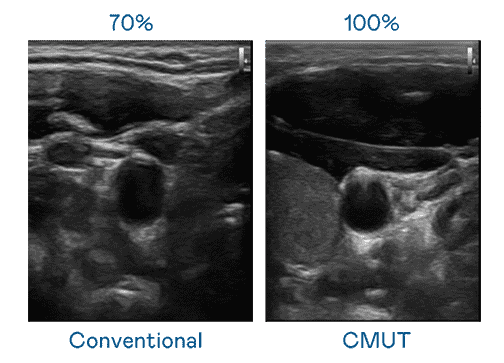

CMUT 技术是一种用电容式微机电元件来产生超音波讯号的技术。。。与传统 PZT 压电式技术相比,,,CMUT 频宽增加 30%,,,,更宽频的超音波讯号让影像解析度大幅提升,,是实现高影像品质医疗超音波扫描、、、促进精准医疗发展的关键技术。。

大频宽带来超清晰影像

超音波影像的解析度高低,,首先取决于探头能发出的讯号频宽。。2468BET CMUT 可提供高清晰的超音波讯号,,,,提供高频宽、、高灵敏度、、影像纹理细节更高的超音波影像,,,协助医护人员缩短影像判读时间及利用精准的医疗影像进行诊断。。。。